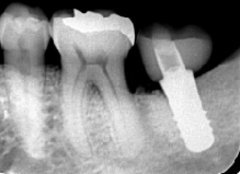

歯周病が進行し、グラグラして物が嚙めず、抜歯してインプラントにしていくことに。

インプラントはストローマンを使用、上部構造はジルコニアセラミックス